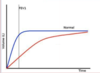

Contrast clinical findings in presentations of restrictive and obstructive lung processes.

- Does this describe obstructive or restrictive lung disease?

- Blue is normal

obstructive